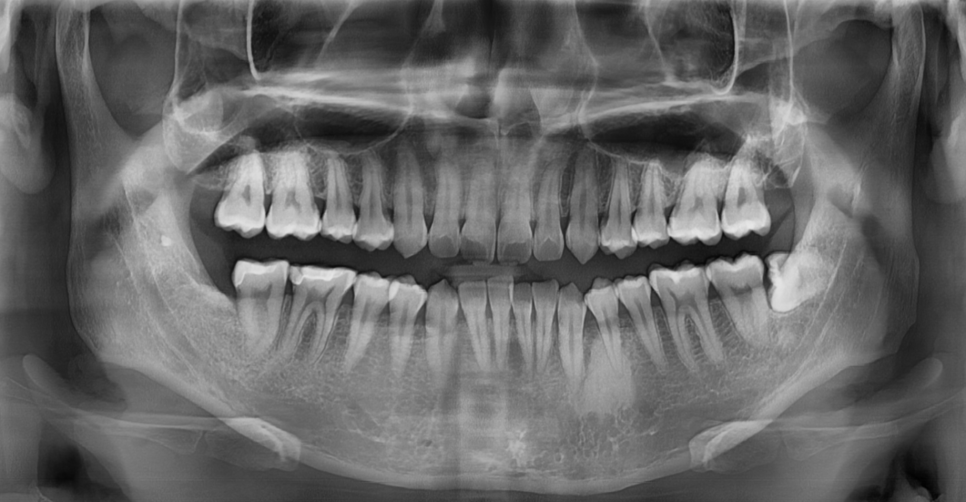

240827 시간이 지나 발치한 부위가 뼈로 잘 찼어요.

환자분이 발치한 부위를 보아도

잘 모르는 경우가 많습니다.

사랑니 부위는 맨 끝쪽이라 안보이기도 하고요.